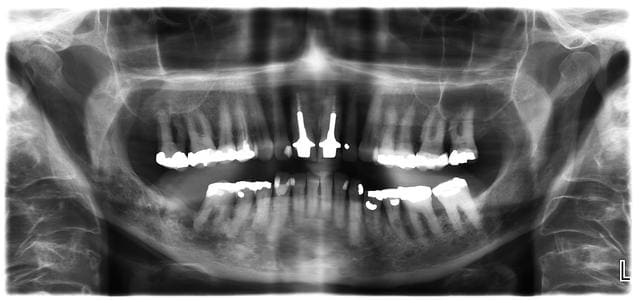

Patiente de 68 qui vient pour douleurs recurrentes depuis 5 mois au niveau de 46.

Radiotherapie pour cancer des amygdales il y a 20 ans...cancer du sein il y a 5 ans. Se dit aujourd hui en bonne sante et controlee regulierement.

Votre diagnostic, et precautions a prendre avant extraction de 46?

j'aime pas trop ce que je vois à la pano secteur 4...l'os me semble bizarre...ou alors la pano est mauvaise...

de plus radiothérapie de la sphère ORL donc =>j'adresse au service ORL/stomato car il y a un risque non négligeable d'avoir une ostéoradionécrose avec la chir...si c'est pas déjà çà qui est responsable du problème sur cette 46...

Osteoradionecrose+infection peri apicale 46, on extraie la semaine prochaine. La patiente veut pas se taper les 20 sceances d oxygenotherapie en caisson hyperbare et les 10 autres post ex.

Et vu la photo, il y a déjà une zone d'ostéo-nécrose, selon la taille du séquestre osseux, il va falloir retirer une bonne quantité d'os.